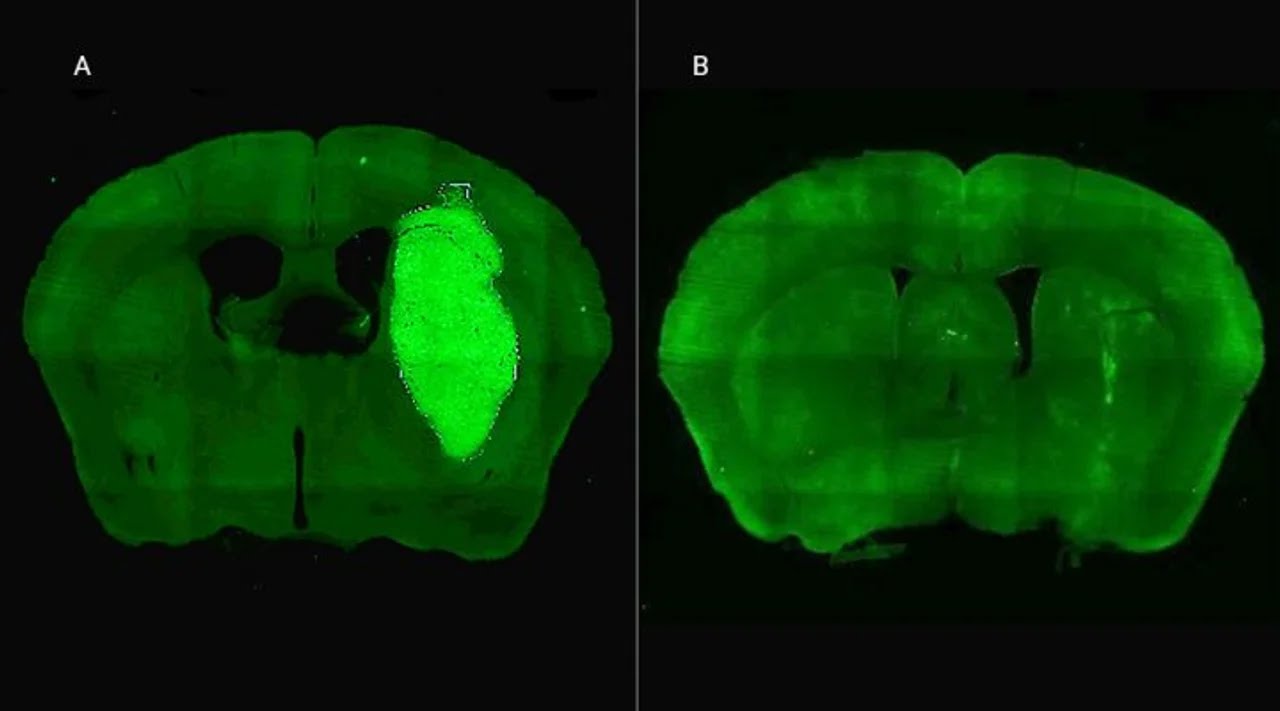

En la imagen A) Se visualiza el tumor cerebral en un modelo preclínico. B) El tumor desaparece gracias a la administración de la estrategia terapéutica diseñada por los especialistas del CONICET.